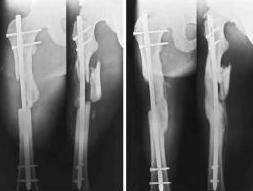

Здравствуйте , уважаемые коллеги. Обратился пациент, мужчина 42лет. для дальнейшего

лечения. Травма 11.09., ДТП.

15.09 проведено оперативное лечение (Блокирующий стержень левого

бедра - статическая система. Открытое вправление вывиха в суставе

Лисфранка и фиксация мет. фиксаторами.)

1. По бедру... Стержень конечно тонковат, торчит в колено..не совсем ясно, что там с прокстимальным блоком(... Если не будет нагрузки, получите замедленное стащение, потом когда датите нагрузку получите перелом винтов (в лучшем случае), штифта - в худшем(

То, что перелом распространяется на сустав не имеет никакого значения и влияния (в данном конкретном примере) для отсрочки динамизации и нагрузки.